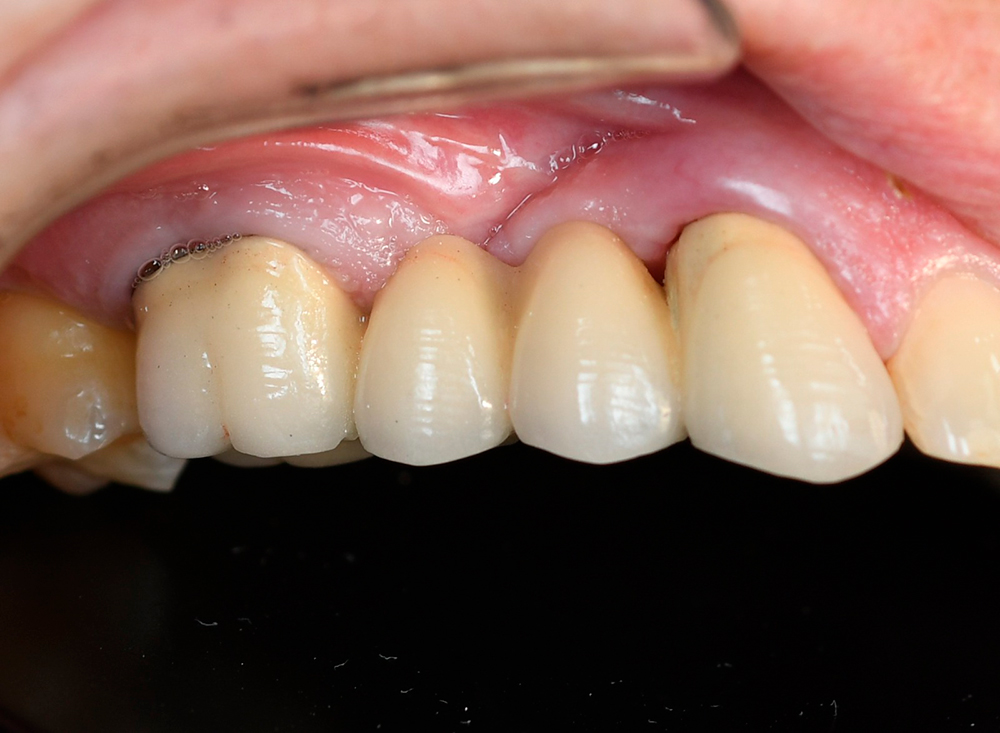

Dear colleagues, I would like to share a clinical case that I have been observing since 2017. A patient came to the clinic with complaints of swelling and pain in the area 1.3, 1.4, 1.5. Conservative therapy was suggested, and after dealing with the acute period, a surgical procedure including cleaning of the periodontal pocket, scaling and root planing and filling the bone pocket with DSI Syntoss Plus that contains beta-tricalcium phosphate granules. The procedure was performed in 2017, the old bridge was replaced with a new one, which is fixed with temporary cement for regular revision due to the unstable condition of 2.6. The patient is unable to undergo implantation for a number of reasons, so the 2.6 will be kept until the last possible moment. Its mobility is grade 2 and the condition of the mucosa can be seen in the photo. The whole process of bone maturation is shown on the x-rays. Thank you for your attention.